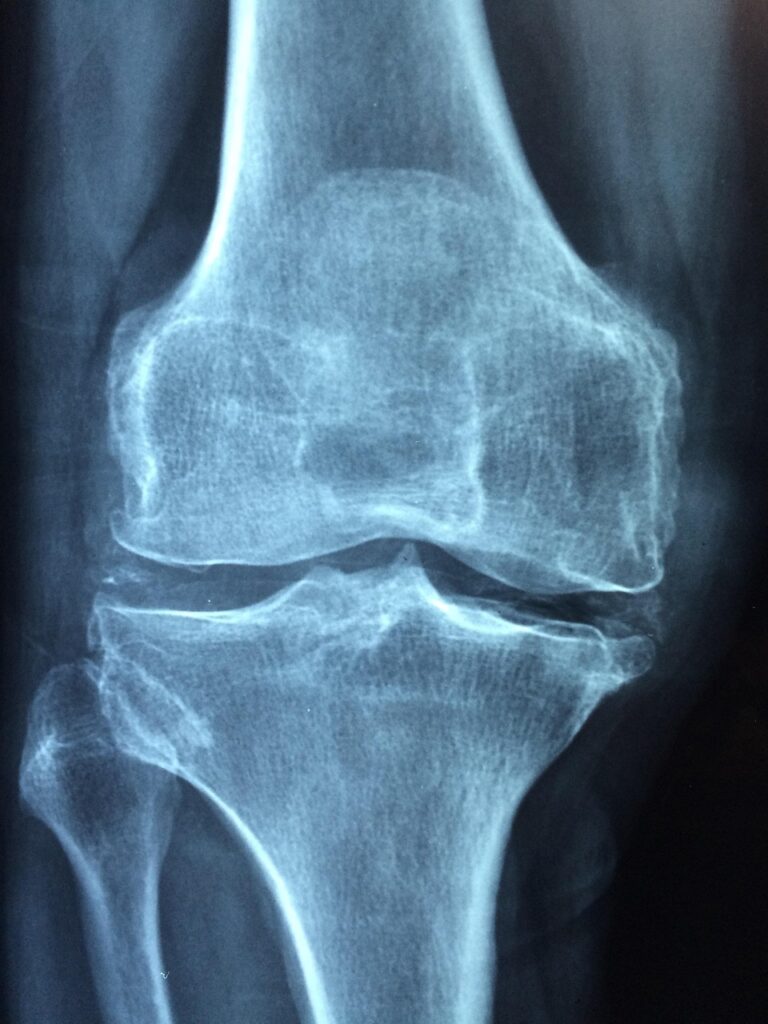

膝痛に悩むあなた、日常生活に支障をきたすほどの痛みを感じているかもしれませんね。膝の痛みは加齢や運動不足、過度な負荷が原因で起こることが多いです。そこで、最近注目されているのが「グルコサミン」です。グルコサミンは関節の健康をサポートする成分として知られていますが、実際にどのように膝痛に効果があるのでしょうか。

まず、グルコサミンは体内で自然に生成されるアミノ糖の一種です。関節軟骨の構成成分として、軟骨の修復や再生を助ける役割を果たしています。膝痛を抱える方にとって、グルコサミンは非常に重要な栄養素と言えるでしょう。

膝痛は、年齢や運動習慣に関わらず多くの方が抱える悩みです。特に、加齢による関節の摩耗や、運動不足による筋力低下が影響を与えることが多いです。あなたも、膝痛のために生活の質が下がっていると感じているのではないでしょうか。そんなあなたに、少しでもお力になれればと思っています。